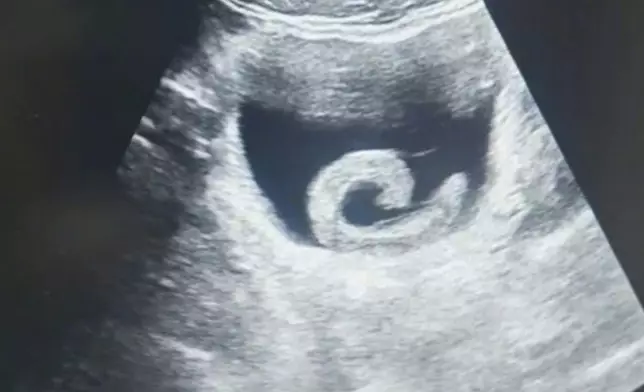

事發後,男子隨即到鄭州市人民醫院求診。超聲波檢查顯示,他的膀胱內出現一條正在蠕動的條索狀異物,周圍並伴隨明顯出血跡象。醫生隨即為他進行「經尿道膀胱異物取出術」,在手術中發現一條約5至6CM長的活體水蛭正緊緊吸附在膀胱黏膜上,吸盤位置已出現嚴重充血、水腫及持續滲血情況。醫護人員成功將這條已吸飽血的水蛭取出後,男子的尿道梗阻問題即時解除,疼痛也隨之消失。